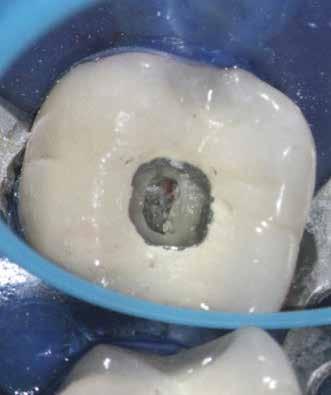

Esetbemutatás (1.)

Egy 63 éves páciens korábban már kezelt bal alsó első nagyőrlőfogából (3.6) eredő mérsékelt fájdalom miatt kereste fel rendelőnket. A kórtörténetében panasza szempontjából releváns információ nem szerepelt. Az elkészült CBCT-felvételen a korábbi kezelések során észre nem vett, jelenleg feltáratlan meziobuccalis csatornát, valamint a mezialis és distalis gyökerek körül kialakult periapicalis elváltozást, és ezt a léziót borító intakt buccalis corticalis csontlemezt láttunk.

A fog revideálását és újbóli gyökértömését két ülésben végeztük el. A régi gyökértömés eltávolítását, valamint mindhárom gyökércsatorna megmunkálását és fertőtlenítését követően kalcium-hidroxid alapú gyógyszeres zárást helyeztünk a gyökércsatornákba. A gyökértömés egy héttel később került behelyezésre. A páciens panaszai két hónap elteltével sem szűntek.

Klinikai vizsgálat során vertikális kopogtatási érzékenységet jelzett. A fog körül mérhető szondázási mélység és a fogmobilitás fiziológiás volt. A CBCT-felvételen nem észleltünk a csontos regeneráció megindulására utaló jeleket (1. a–c. ábrák). A korábban gyökérkezelt, gyökértömött és revideált 3.6-os fog esetében az alábbi diagnózis került felállításra: periodontitis periapicalis symptomatica. A panaszokat okozó fog további ellátása során navigált endodonciai mikrosebészetet kívántunk alkalmazni. Az alsó állcsontról intraorális szkent (TRIOS, 3Shape) készítettünk, és a felszíni topográfiát tartalmazó STL fájlt, valamint a CBCT-felvétel készítése során nyert DICOM fájlokat a Blue Sky Bio szoftver segítségével egyesítettük. A sebészi sablon megtervezésére az így kapott háromdimenziós képet használtuk. A sablon kialakítása során arra törekedtünk, hogy a sablon egyértelműen meghatározza a gyökércsúcsi terület eléréséhez szükséges csontablak határait (1. d. ábra)